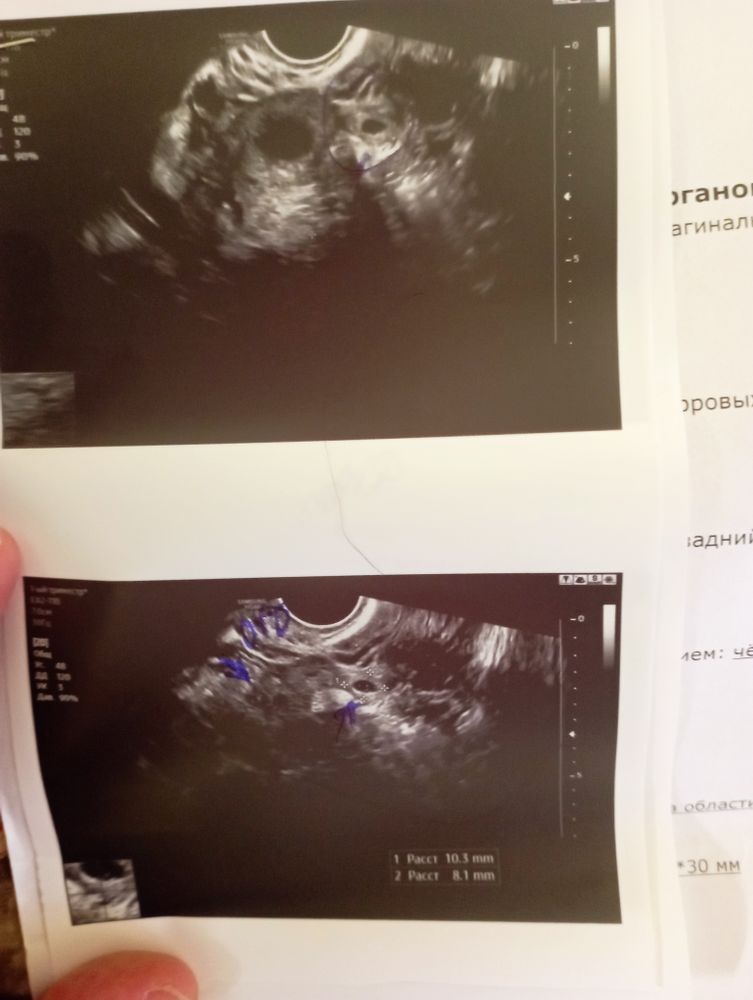

Изображение Анна Шевченко,

К сожалению нет. Данная беременность патологична.